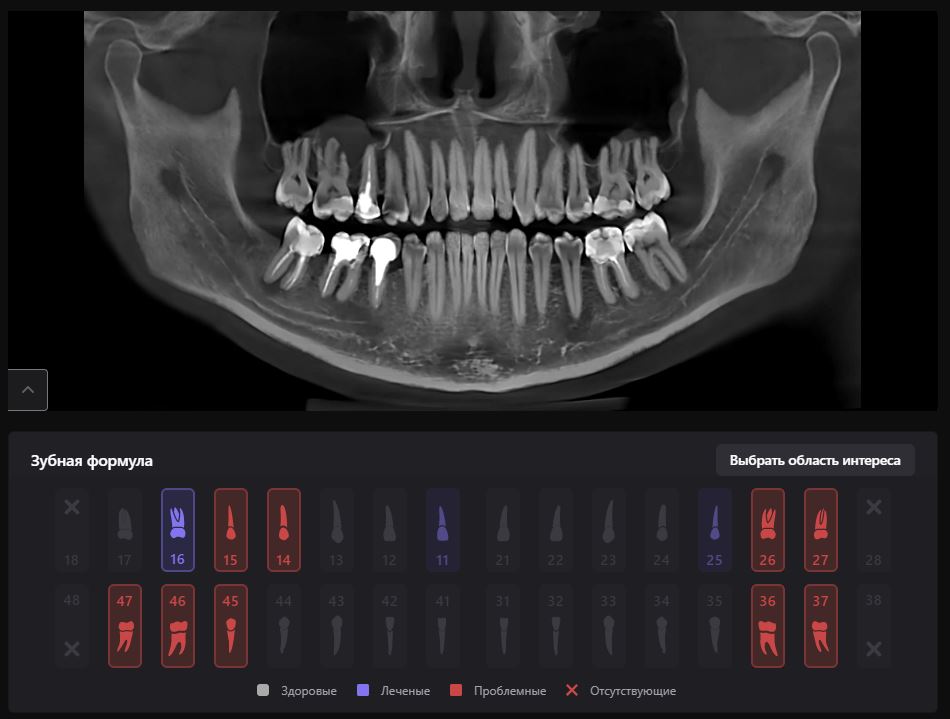

Фотографии ортопантомограмм и работ Родена